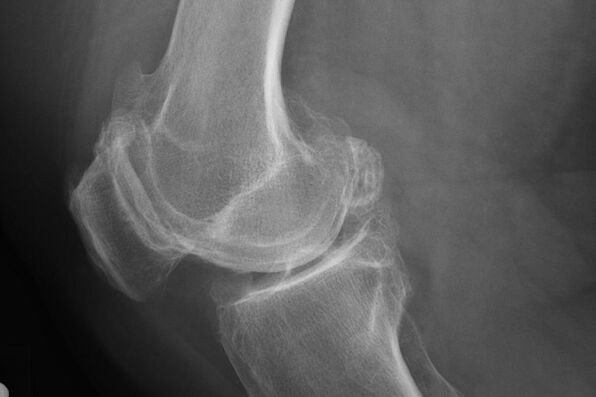

Sebagai aturan, diagnosis penyakit pada tahap ini terjadi secara tidak sengaja, selama x -ray. Di atasnya, dokter mungkin mencatat beberapa penyimpangan pada tulang rawan. Dimungkinkan juga untuk mempersempit lumen di antara bagian -bagian sambungan.

X -Ray akan membantu mengidentifikasi penyimpangan dalam tulang rawan.

Setelah pemeriksaan, dokter meresepkan radiografi pasien. Ini adalah metode utama mendiagnosis arthrosis sendi lutut dari derajat apa pun.

X -Ray memberi dokter gagasan tentang perubahan yang terjadi di tulang rawan sendi. Namun, dalam beberapa kasus, tahap awal mungkin tidak didefinisikan dalam gambar.

Jika perlu, dokter dapat meresepkan bagian berulang dari sinar-X atau tomografi resonansi magnetik dan magnetik.